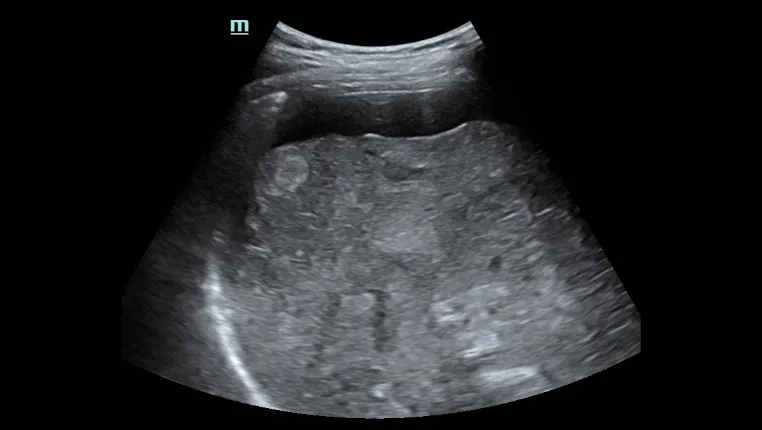

Пункция печени под контролем ультразвука

Асцит печени